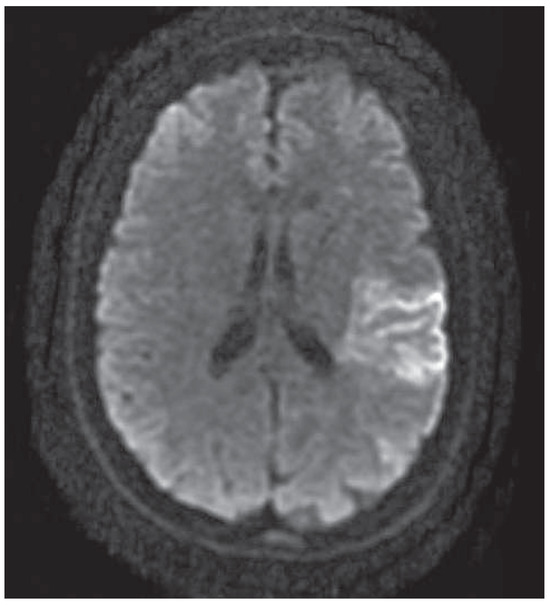

Mechanical Thrombectomy After Embolic Internal Carotid Artery Occlusion in Acute Stroke

Case presentation